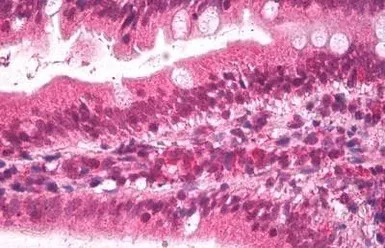

IHC-P analysis of human small intestine using GTX88654 Apolipoprotein B antibody, Internal.

Antigen retrieval : citrate buffer pH 6

Dilution : 2μg/ml